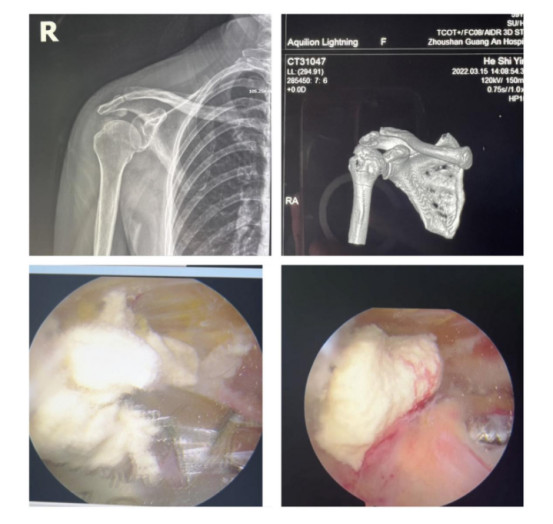

賀大媽慕名來(lái)廣安醫(yī)院找羅軍主任就診,面對(duì)羅醫(yī)生,賀大媽哭訴:“羅醫(yī)生,我真想剁下自己的這只胳膊。”羅軍主任根據(jù)患者的癥狀拍片,診斷為岡上肌鈣化性肌腱炎,隨后,羅醫(yī)生為李大媽進(jìn)行了肩關(guān)節(jié)鏡微創(chuàng)手術(shù),竟從她的右肩“擠”出“牙膏”。

鈣化性肌腱炎是一種自限性疾病,就是疾病發(fā)生發(fā)展到一定程度后,經(jīng)長(zhǎng)期機(jī)體調(diào)節(jié)能夠控制病情發(fā)展并逐漸恢復(fù)痊愈。它分為四個(gè)階段:鈣化前期、鈣化形成期、鈣化吸收期、鈣化后期,往往在“鈣鹽斑塊”吸收時(shí),疼痛最劇烈,賀大媽就正處于“吸收期”。

羅軍主任表示,很多人會(huì)把肩痛都?xì)w因于肩周炎,這是一個(gè)很大的誤區(qū)。其實(shí),肩痛人群中只有15%左右是肩周炎,大部分肩膀疼痛由于肩袖損傷、肩峰撞擊征、鈣化性肌腱炎。而大多數(shù)人也因此認(rèn)為忍一忍就會(huì)自愈,常常延誤治療,關(guān)節(jié)鏡微創(chuàng)治療鈣化性肌腱炎,可以快速緩解疼痛,同時(shí)可以修復(fù)肩袖損傷,清理肩膀骨刺。